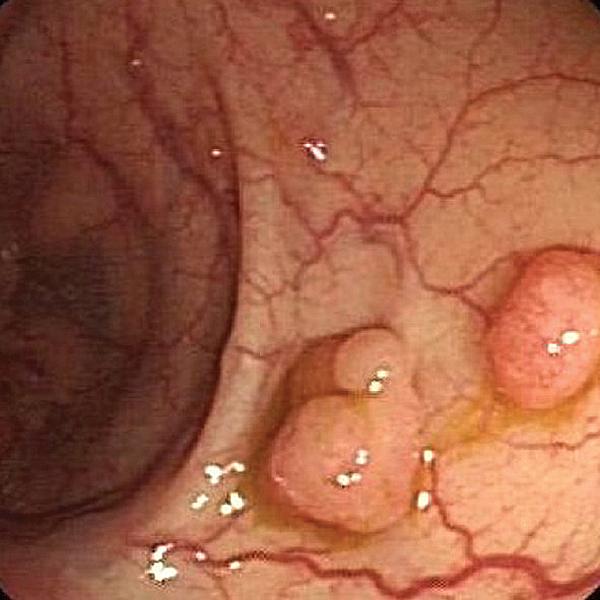

2、多发性胃肠息肉:息肉可发生于整个胃肠道,数目多少不等,息肉大多表面光滑,呈桑堪状或分叶状。带蒂或者无蒂,大多为炎性息肉,错构瘤。